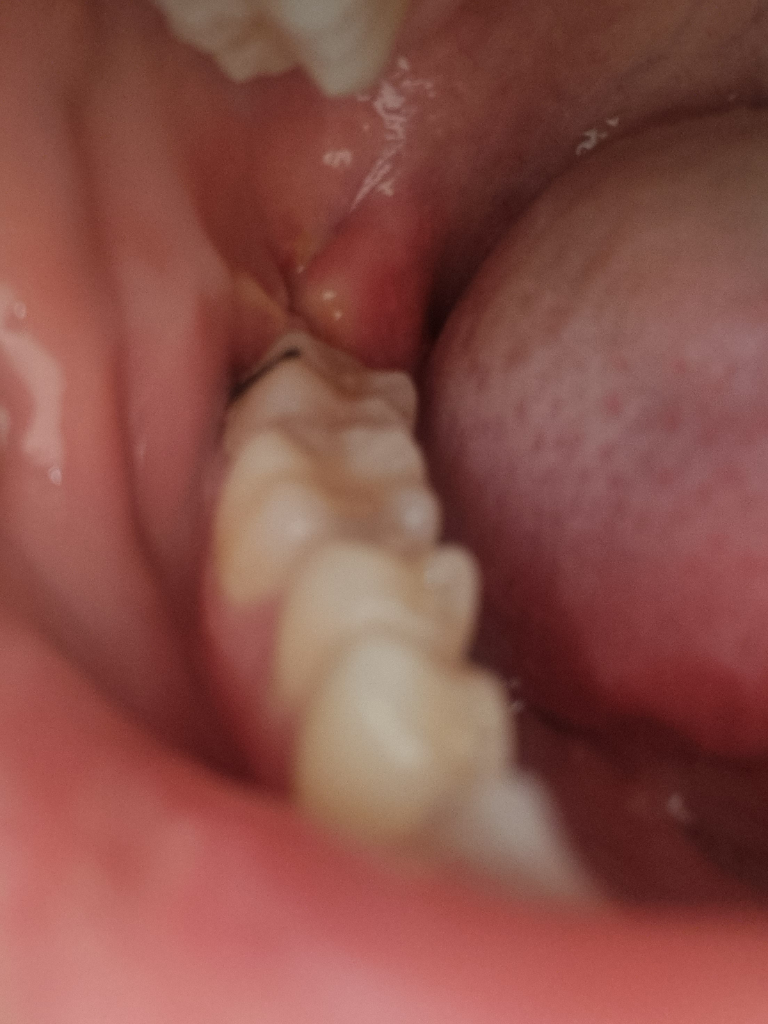

사랑니 발치 후 5일차에 실밥이 조금 풀렸어요ㅠㅠ

원래는 어금니 옆쪽 잇몸이랑 붙어있었는데 이렇게 떨어져버렸어요.. 냅둬야하나요 아니면 빠르게 치과를 가야하나요?? 완전히 떨어진건 아닌것같은데.. 정상인가요...?

• 1번 째 사진

그래도 내버려 두셔도 됩니다. 잘 낫고 있는 것으로 보이며 실밥 뽑으시는 날에 치과 가보시면 됩니다.

사랑니 발치 이후 봉합은 생각보다 긴밀하게 하지 않습니다. 노폐물이나 염증 산물이 외부로 배출될 수 있게끔 느슨하게 하는 경우도 많습니다. 따라서 불편감이 없는 상태에서 단순히 실밥이 조금 풀린 것은 걱정하지 않아도 됩니다.

실밥이 풀렷어도 크게 문제가 되지 않습니다. 지혈만 잘되신상태라면 걱정하지 않으셔도 됩니다.

1주일 보다는 조금 빨리 풀리기는 하였으나, 5일 정도 상처부위가 봉합되어 있었다면 부족하지는 않습니다.

사랑니 발치 후 5일차에 실밥이 조금 풀린 경우 크게 문제가 되지는 않습니다. 봉합부위가 벌어지거나 출혈 및 통증이 있는 경우에는 치과 방문이 필요로 됩니다.

사진상으론 크게 문제가 없어보입니다. 보통 사랑니 발치 후에는 1~2주 정도 잇몸 초기 치유기간이 걸립니다. 그 시기가 지나면 잇몸 구멍은 어느정도 메워지게 됩니다